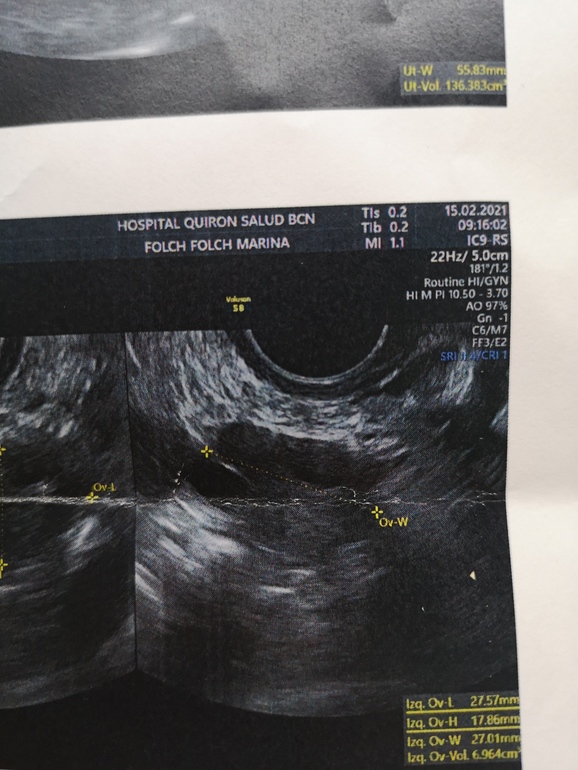

Фото скину, а заключение не на русском, не поймёте)) Единственное пя был увеличен в 2 раза, у меня так бывает там где дф или О, первая фото пя